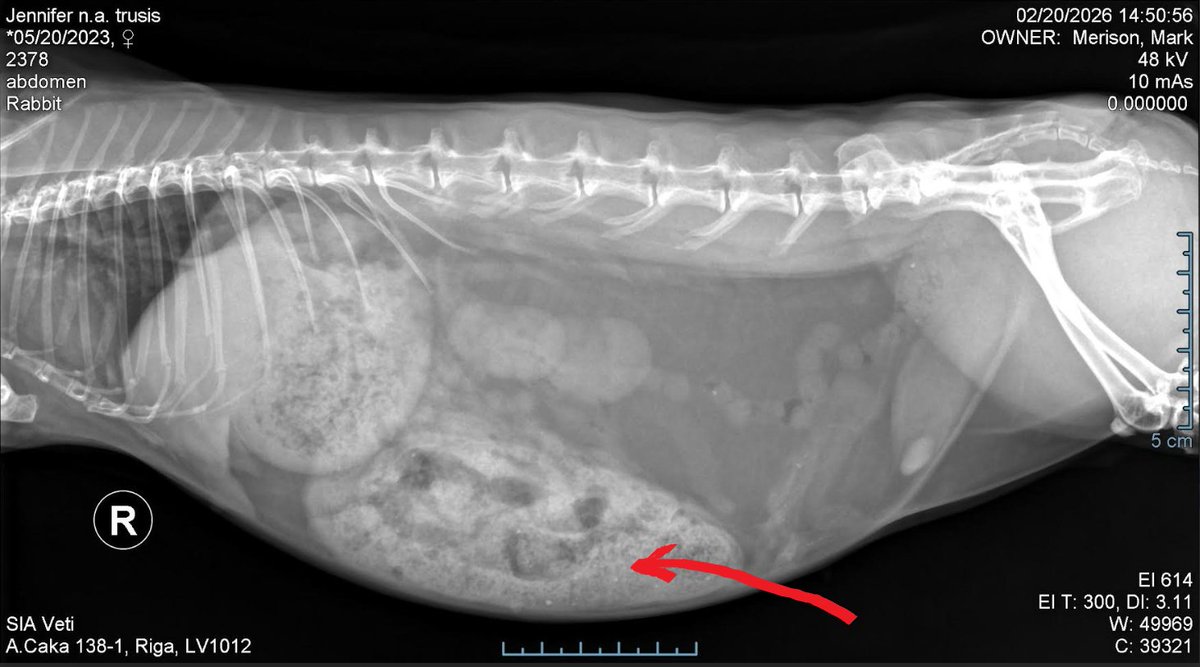

Please wish Jenny a huge bundle of positive thoughts and prayers. She's fighting hard to beat the problem happening with her stomach.

The X ray taken last Friday shows abnormalities with her lower intestine and she's being a good girl, tolerating being medicated with five different meds twice a day.

I've drawn an arrow on the photo detailing the area of her stomach in question.

Thankfully, with care and continued medication, and lots of gentle massages she'll be well again.